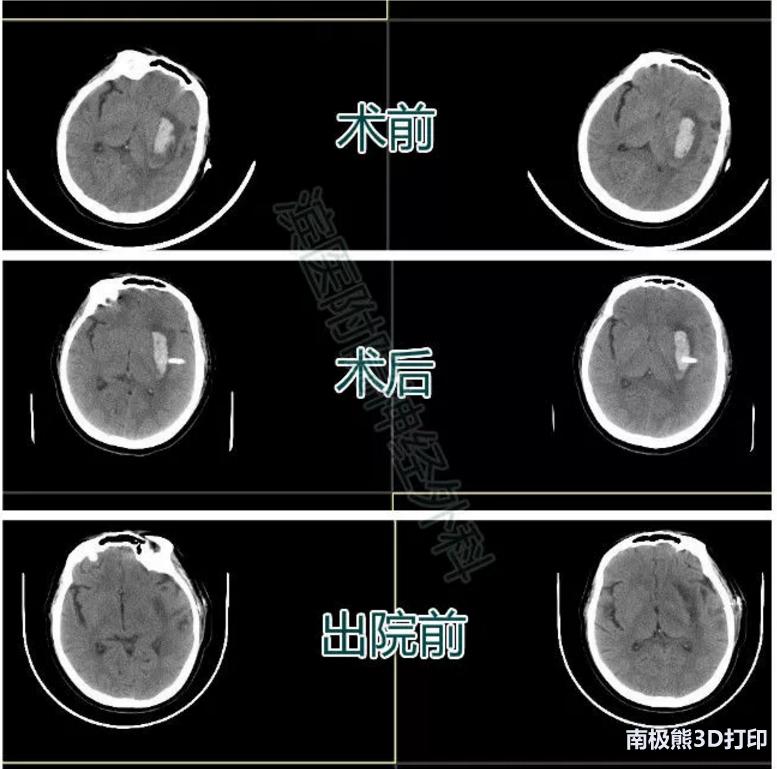

患者李某某,女,46岁,因“突发言语障碍及右侧肢体活动不利1天”入院。

入院查体:嗜睡状态,言语不清。双瞳孔直径约2mm,对光反应灵敏,右上肢肌力1级,右下肢肌力2级,左侧肢体肌力5级。颅脑CT示左侧基底节区脑出血。入院后排除手术禁忌症,行3D导板下经颞部微创血肿穿刺,术后复查CT如图,引流管位置满意。12天后复查颅脑CT血肿完全吸收,患者右侧肢体肌力恢复到4级,生活自理。

患者一影像资料